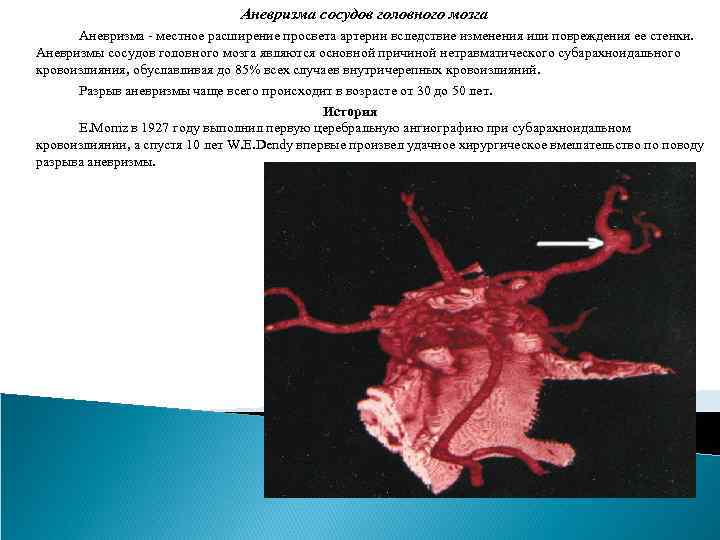

Аневризма сосудов головного мозга Аневризма - местное расширение просвета артерии вследствие изменения или повреждения ее стенки. Аневризмы сосудов головного мозга являются основной причиной нетравматического субарахноидального кровоизлияния, обуславливая до 85% всех случаев внутричерепных кровоизлияний. Разрыв аневризмы чаще всего происходит в возрасте от 30 до 50 лет. История Е. Moniz в 1927 году выполнил первую церебральную ангиографию при субарахноидальном кровоизлиянии, а спустя 10 лет W. E. Dendy впервые произвел удачное хирургическое вмешательство по поводу разрыва аневризмы.